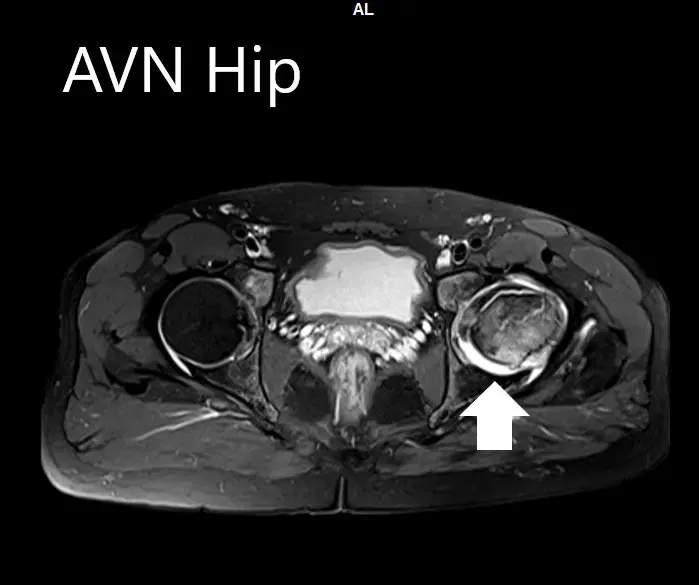

Se realizó una resonancia magnética para confirmar el diagnóstico y la estadificación de la enfermedad. La cabeza femoral izquierda estaba colapsada con contorno irregular y mostraba áreas de intensidad de señal alterada con una línea de demarcación. Zonas hipointensas tanto en T1WI como T2WI observadas en la cabeza sugestivas de esclerosis. Se observó edema de médula circundante

La cadera izquierda presentaba necrosis avascular avanzada con colapso. La cadera derecha no estaba afectada en ese momento. Recibió formación sobre el agravamiento del colapso de la articulación de la cadera que provocaba sus síntomas. Aunque el paciente era joven, se le recomendó una cirugía de reemplazo total de cadera debido al colapso de la cabeza del fémur por artritis.